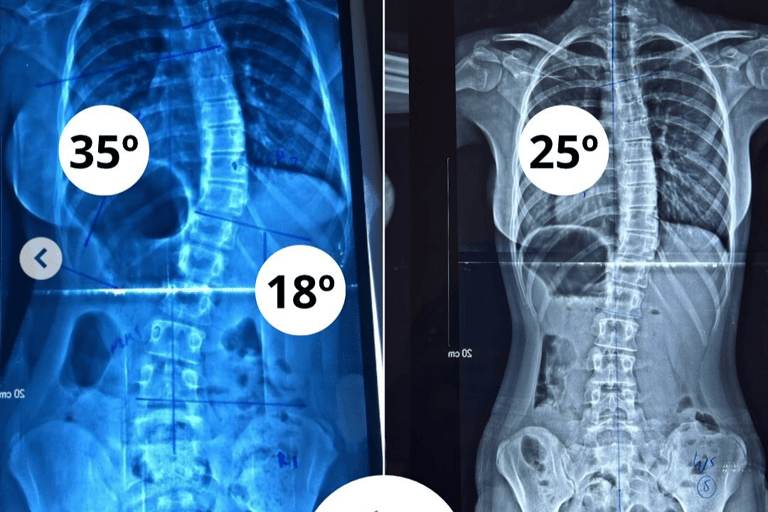

Resultado de 18 Meses de Tratamento S4D paciente com Escoliose Idiopática Infantil de Barra do Choça – BA.

Avaliação Inicial: 35 de curva torácica 18° de curva lombar e Risser 0

Reavaliação 36 meses: está com 25° de curva torácica, e Risser ⅘.